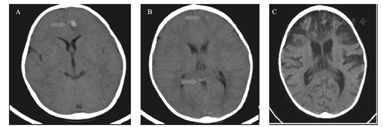

辅助检查:(1)脑电图:入院当日视频脑电图:背景节律减慢(双半球弥漫性2~3 Hz中波幅δ活动为主,夹杂4~6 Hz中波幅θ活动),弥漫性慢波,双额、左颞区尖波、尖慢波、多形性慢波周期性发放,左额为著,清醒期左顶尖波散发,监测到数次临床及临床下电发作。出院时动态脑电图:异常幼儿脑电图(背景活动为弥漫性δ波,睡眠期右侧中央、顶区、左侧顶区棘慢波、尖慢波非同步发放)。(2)头部影像学:入院当天头CT提示颅内出血(图1)。第2天头部MRI符合出血性脑炎表现(图2)。第17天头MRI示双侧额叶、左颞、顶叶弥漫病变,脑炎恢复期改变,左脑额叶脑出血范围较前缩小。弥散成像未见确切异常(图3)。(3)其他:双耳客观听阈检查正常,脑干听觉诱发电位正常,肝胆脾超声正常,双眼闪光视觉诱发电位正常。

A:入院当天头部CT示左侧额叶多发斑片状高密度影,周围见片状稍低密度影,左侧额叶多发出血灶;B、C:第27天头部CT示双侧额叶、顶叶、左侧颞叶见大面积低密度影,内散在点片状稍高密度影;左侧丘脑、双侧基底节区散在点片状低密度影;双侧侧脑室、第三脑室扩张。双侧基底节区腔梗。